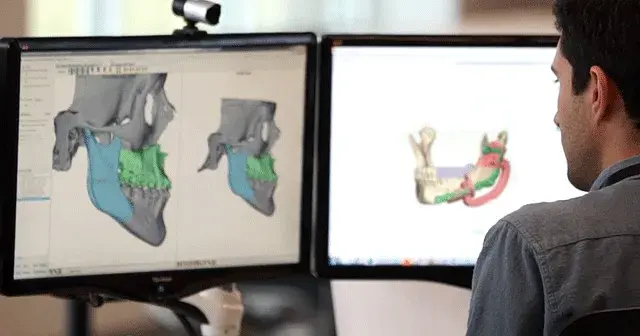

3D Systems partners with device manufacturers and healthcare providers to transform surgical outcomes for both patients and surgeons. We create custom solutions that help translate virtual surgery into the OR with the goal of improving outcomes and the overall patient experience. Our multifaceted offerings include advanced design and planning software, expert planning services and a full range of custom implants and instrumentation.